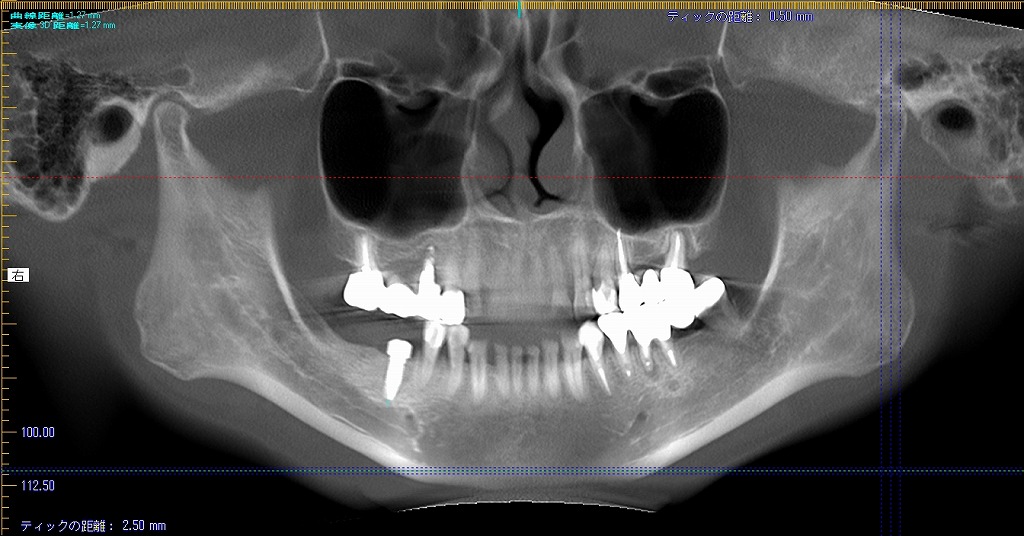

埋入前のCTの審査になります

これと術中の審査のCTがすべてです

埋入後のCTになります

距離がないことがわかります

わずか1mm、2mmの世界の勝負なためいつもいい緊張感

にて行っています